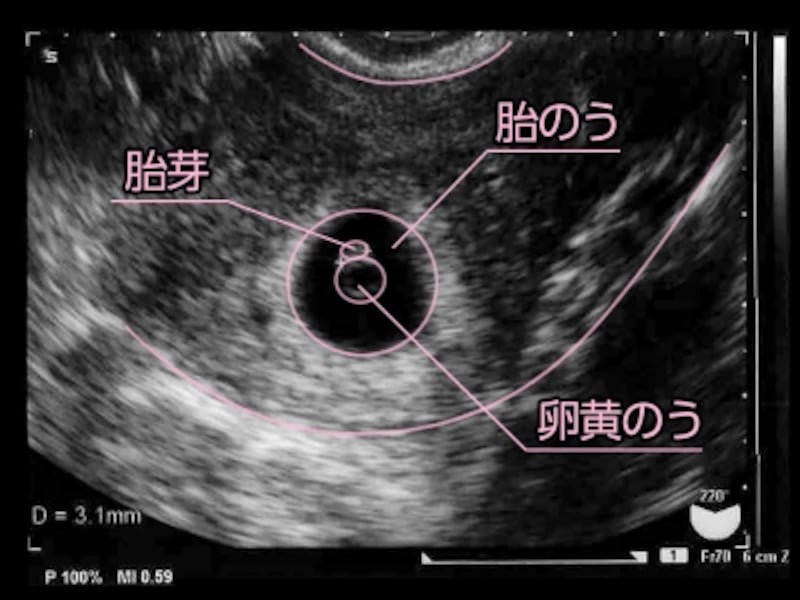

5 産科一般超音波検査 初期編 正常所見4 7週 日本産婦人科医会

5 産科一般超音波検査 初期編 正常所見4 7週 日本産婦人科医会

5 産科一般超音波検査 初期編 正常所見4 7週 日本産婦人科医会

5 産科一般超音波検査 初期編 正常所見4 7週 日本産婦人科医会

超音波写真館 妊娠初期4 7週 超音波教室 ママニティ大百科

妊娠7週目 胎芽 胎嚢のエコー写真や大きさ つわりや流産 妊娠初期 All About